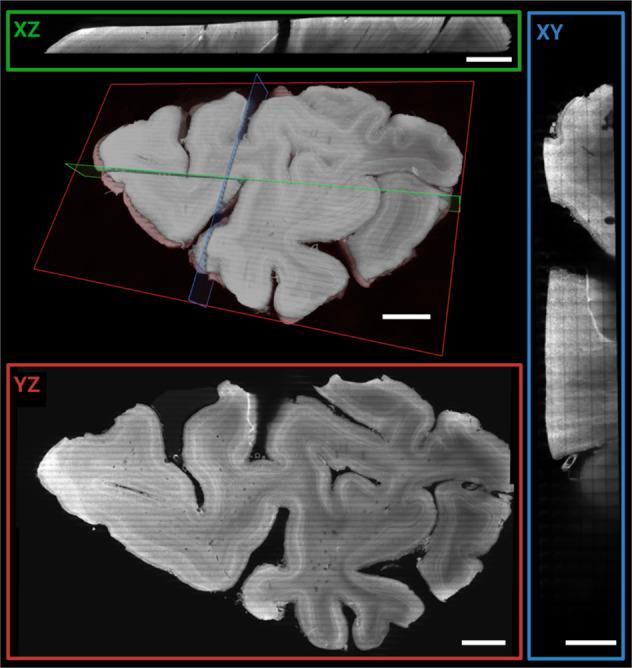

The ability to image human tissue samples in 3D, with both cellular resolution and a large field of view (FOV), can improve fundamental and clinical investigations. Here, we demonstrate the feasibility of light-sheet imaging of ~5 cm sized formalin fixed human brain and up to ~7 cm sized formalin fixed paraffin embedded (FFPE) prostate cancer samples, processed with the FFPE-MASH protocol. We present a light-sheet microscopy prototype, the cleared-tissue dual view Selective Plane Illumination Microscope (ct-dSPIM), capable of fast 3D high-resolution acquisitions of cm scale cleared tissue. We used mosaic scans for fast 3D overviews of entire tissue samples or higher resolution overviews of large ROIs with various speeds: (a) Mosaic 16 (16.4 µm isotropic resolution, ~1.7 h/cm), (b) Mosaic 4 (4.1 µm isotropic resolution, ~ 5 h/cm) and (c) Mosaic 0.5 (0.5 µm near isotropic resolution, ~15.8 h/cm). We could visualise cortical layers and neurons around the border of human brain areas V1&V2, and could demonstrate suitable imaging quality for Gleason score grading in thick prostate cancer samples. We show that ct-dSPIM imaging is an excellent technique to quantitatively assess entire MASH prepared large-scale human tissue samples in 3D, with considerable future clinical potential.